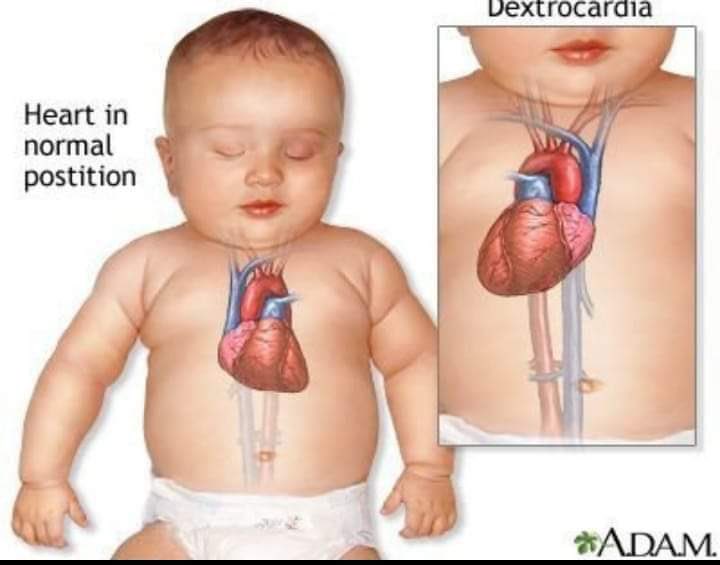

4- بعد هذه المعلومات دعوني أخبركم لماذا فقط معظم الأشخاص وليس كلهم ينطبق عليهم هذا التشريح القلبى؟

هذا نتيجة وجود بعض العيوب الخلقية مثل

القلب اليميني (Dextrocardia) عبارة عن حالة طبية نادرة يكون فيها القلب أقرب إلى الجهة اليمنى من الجسم بدلاً من يساره. القلب اليميني عبارة عن عيب خلقي، بمعنى أن الشخص يولد بهذا العيب علماً أن نسبة انتشار القلب اليميني لا تتعدى الـ 1% من مجموع سكان العالم.

هذا نتيجة وجود بعض العيوب الخلقية مثل

القلب اليميني (Dextrocardia) عبارة عن حالة طبية نادرة يكون فيها القلب أقرب إلى الجهة اليمنى من الجسم بدلاً من يساره. القلب اليميني عبارة عن عيب خلقي، بمعنى أن الشخص يولد بهذا العيب علماً أن نسبة انتشار القلب اليميني لا تتعدى الـ 1% من مجموع سكان العالم.

أى تغير فى مكان القلب يجعل الشخص يعانى من العديد من المشاكل الصحية فمثلًا فى حالة القلب اليمينى يعانى الطفل فيها من العديد من مشاكل التنفس وضعف فى الدورة الدموية مشاكل النمو وقلة المناعة وغيرها

أى تغير فى مكان القلب يجعل الشخص يعانى من العديد من المشاكل الصحية فمثلًا فى حالة القلب اليمينى يعانى الطفل فيها من العديد من مشاكل التنفس وضعف فى الدورة الدموية مشاكل النمو وقلة المناعة وغيرها